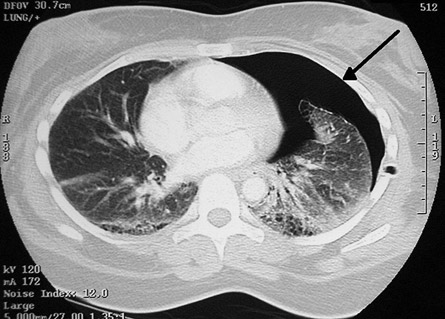

O Pneumotórax é causado por uma lesão na parede do pulmão (também chamada de pleura visceral) em que o ar sai do pulmão (como em uma bexiga furada), porém não retorna para dentro deste, acumulando-se na cavidade. Este acúmulo pode gerar um aumento importante da pressão na cavidade, atrapalhando ou impedindo o pulmão de encher-se de ar, impossibilitando a respiração por aquele pulmão. Também, o aumento da pressão pode ser tão importante a gerar um desvio de todo o mediastino (coração, grandes vasos) para o outro lado, atrapalhando toda função circulatória, podendo causar grave hipotensão e até morte. Este caso é chamado de pneumotórax hipertensivo.

O pneumotórax é classificado quanto a sua causa: espontâneo ou não. Causas de pneumotórax não espontâneo são traumas torácicos, como acidentes veiculares, tiros ou facadas; iatrogênicos, em que um tratamento médico o causa, como na passagem de um catéter em veias profundas ou barotraumas, causados por aumentos das pressões intrapulmonares, por exemplo, em pacientes em ventilação mecânica